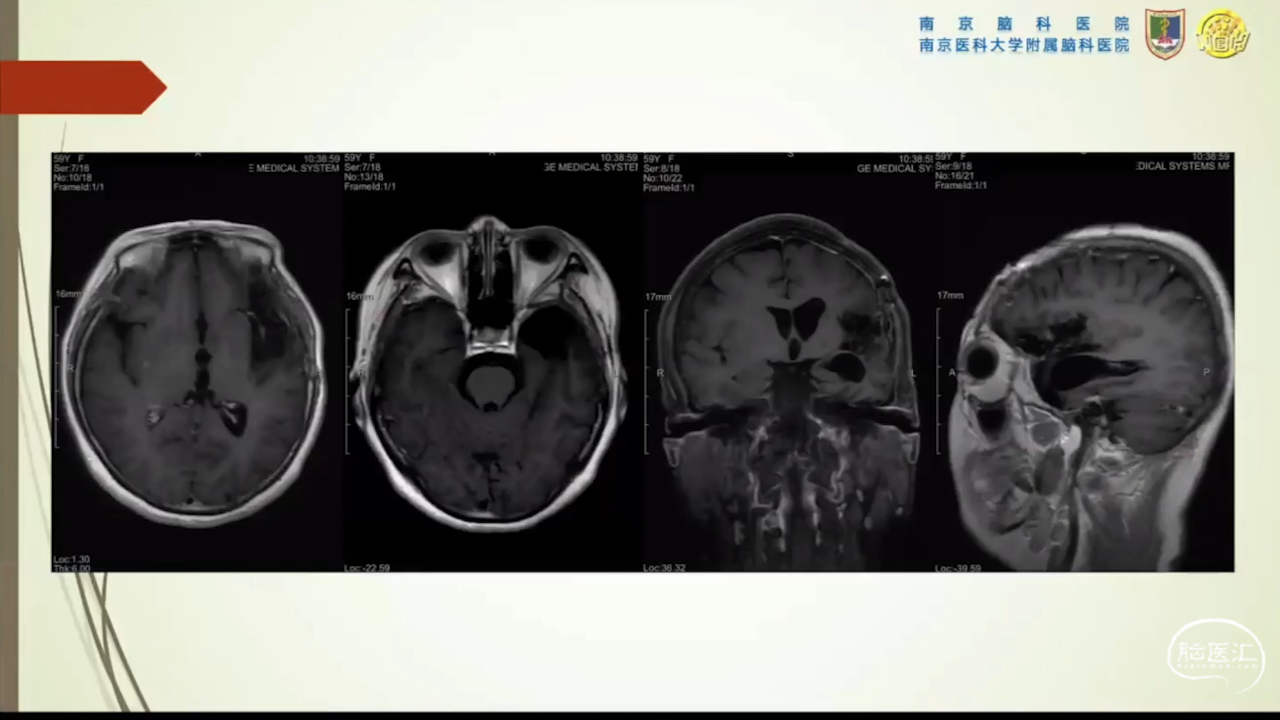

胶质瘤是发病率最高的颅内肿瘤(约占44.69%),岛叶是神经胶质瘤的好发部位,大约有25%的低级别胶质瘤及10%的高级别胶质瘤发生在岛叶,大多数岛叶胶质瘤为低级别胶质瘤。岛叶在调节内脏感觉运动、控制心血管交感活性、传入躯体感觉中均起重要作用。它也参与了痛觉的传递、运动规划、自主性吞咽、味觉、听觉、前庭功能、情绪、认知能力和语言能力。因为岛叶解剖结构复杂,并覆盖有高级语言皮层、白质束及重要的血管结构,故岛叶部位的手术难度极大。

会议内容截图